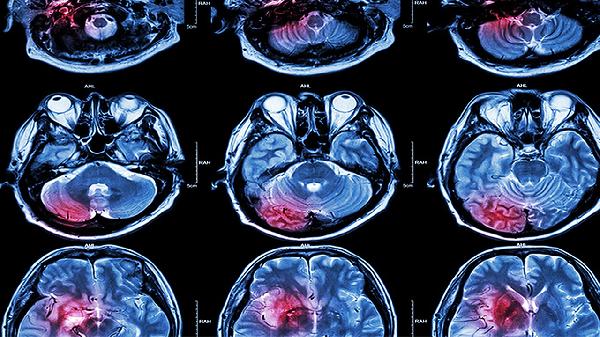

脑部磁共振空泡蝶鞍是什么意思

脑部磁共振空泡蝶鞍是指蝶鞍内出现异常空泡状结构,可能由垂体萎缩、脑脊液压力异常或先天性发育异常等因素引起。